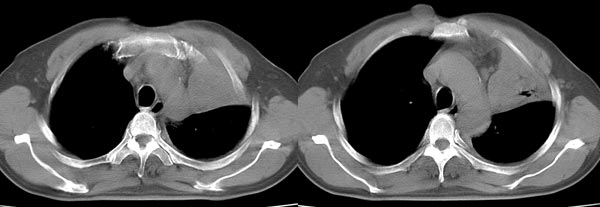

以下是引用dyqct在2006-4-1 22:20:00的发言:[br]左肺上叶明显萎陷、实变,支气管大部通畅,部分扩张,部分壁似见串珠状钙化。主动脉弓旁见肿大淋巴结。纵隔左移。左侧胸壁后缘见新月形高密度,边界清楚。[br] 考虑:1、左肺上叶肺不张伴支气管扩张(牵拉性),可能为支气管内膜结核所致。[br] 2、左侧少量胸腔积液。[br]

以下是引用piao001在2006-4-2 14:13:00的发言:[br]左肺上叶不全性不张,其内见钙化及扩张支气管,结合病史,考虑支气管内膜结核。建议支气管镜明确检查。